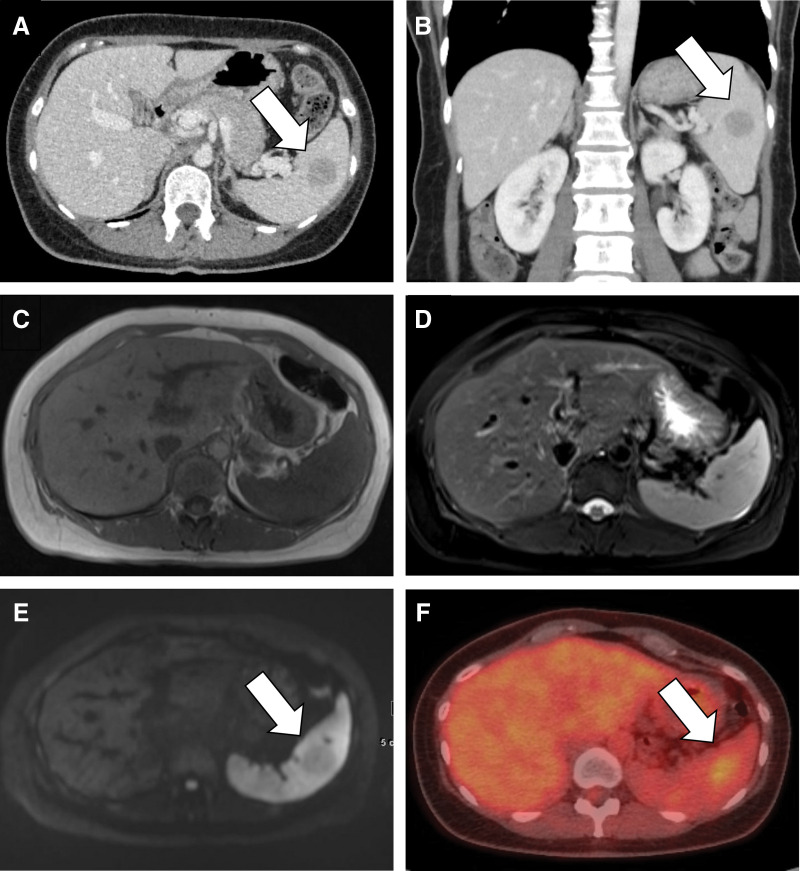

Case presentation: Case 1: A 47-year-old female was found to have a 26 mm tumor in the spleen on abdominal ultrasonography during follow-up for gallbladder polyps. Abdominal computed tomography (CT), magnetic resonance imaging (MRI), and positron emission tomography-CT were performed. EUS-FNA was performed because of the high surgical risk associated with pulmonary hypertension and because hemangioendothelioma, an intermediate malignancy, was suspected. Subsequently, laparoscopic splenectomy was performed, and SANT was diagnosed. Case 2: A 46-year-old female had an incidental detection of a tumor in the spleen on CT. SANT was suspected based on CT and MRI findings. Malignancy could not be completely ruled out owing to the gradual growth of the mass; therefore, the patient was referred to our hospital for surgery. Laparoscopic splenectomy was performed, and SANT was subsequently diagnosed.